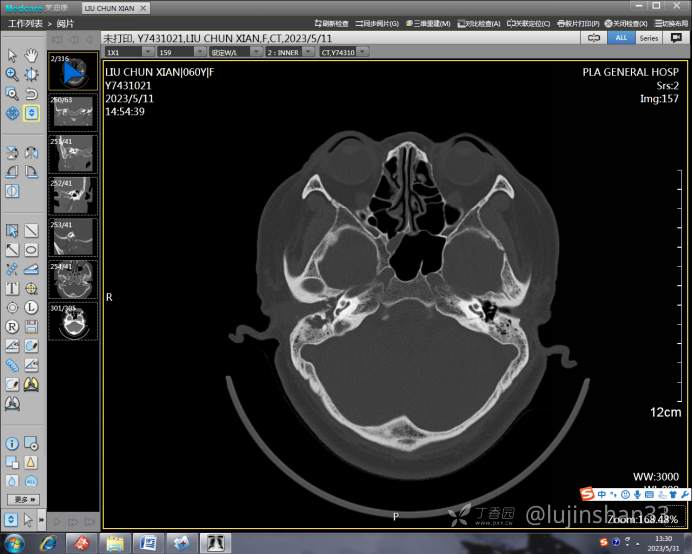

(2023-05-12 10:15,本院)行CT(颅脑)检查提示:右侧颞骨广泛骨质破坏,伴巨大软组织肿块,性质待定,考虑肿瘤性病变,颈静脉球瘤?软骨源性肿瘤?请结合临床及病理进一步明确。